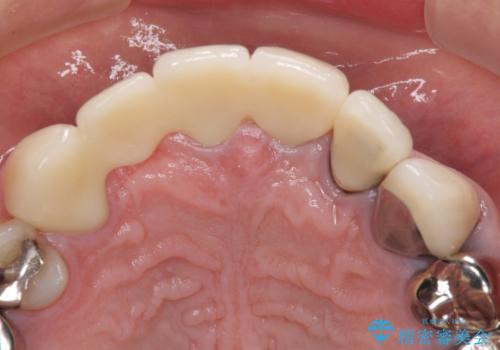

欠けてしまった前歯のブリッジをオールセラミックブリッジへ

犬歯はブリッジの中で虫歯が進行していたため、根管治療からやり直しをした後、オールセラミックブリッジにて補綴することとしました。

歯肉が少し退縮していたため、補綴治療のやり直しにより歯が少し長く見えるようになりましたが、自然な口元に仕上がり、患者様には大変満足していただきました。